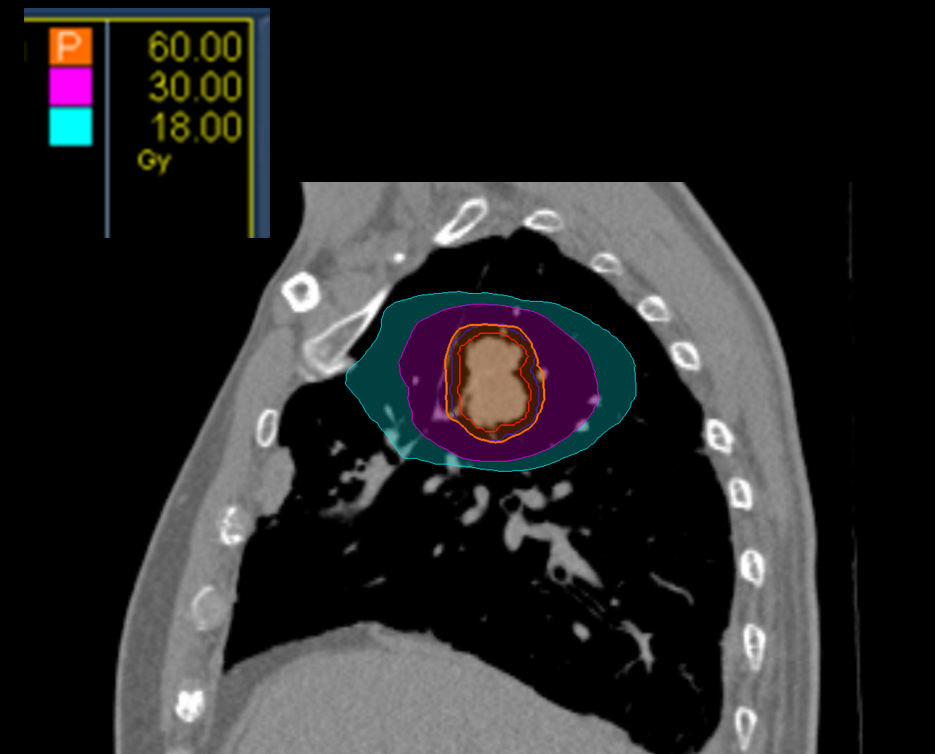

Treatment Plan Images

Treatment Planning Highlights

Fractionation

60 Gy in 8 fractions

PTV(s) Volume

21.8cc

Dose Distributions

- Prescription to the

78.9% isodose line - Max. dose 76.05 Gy

New Conformality Index (nCI)

nCi = 1.22

Gradient Index (GI)

GI = 4.24